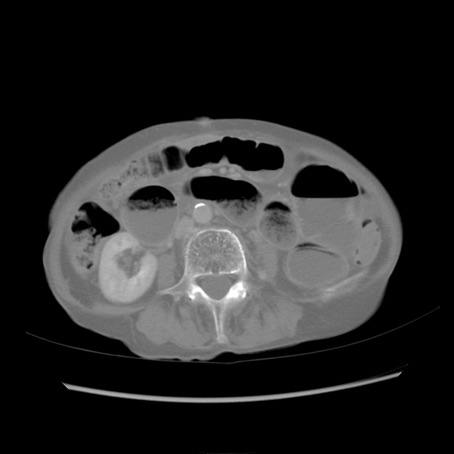

症例25(横断像)

【症例】80歳代女性

【主訴】胸のつかえ感

【現病歴】約9時間前に食後から胸のつかえた感じあり、嘔吐あり、来院。

【既往歴】胃癌(全摘)、胆摘、虫垂炎

【身体所見】心窩部に圧痛あり、反跳痛なし。

【データ】WBC 5700、CRP 0.05